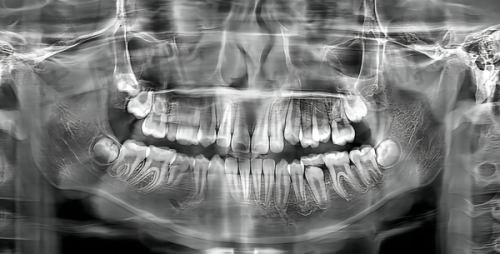

大连奥美口腔成立于2023年12月,门店面积约400平方米,设立有停车场,方便患者到院看诊。医院购置了口腔CT、超声洁治器、高端牙椅、数字化全景X光机、超声洁牙机、冷光美白仪等精良仪器,为牙周治疗提供了有力的技术支持。这些数字化设备能够精细检测牙周疾病的程度和范围,医生可以根据检测结果制定更加科学、个性化的治疗方案。此外,医院已经建立了完善的医疗管理体系,能够提供一站式的口腔诊疗服务,从检查、诊断到治疗,患者无需在多个科室之间奔波,节省了时间和精力。